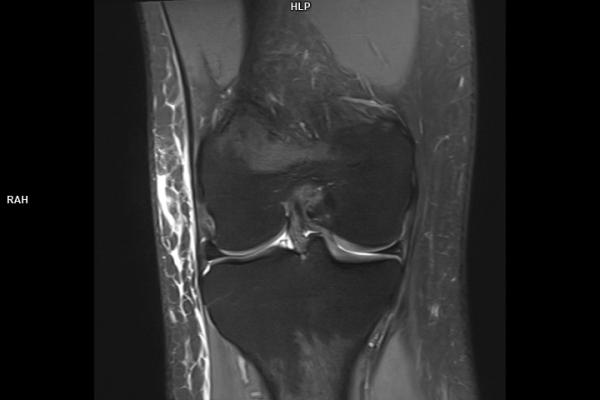

Detailbild MRT

Die MRT (Magnetresonanztomographie) arbeitet mit Magnetfeldern und Radiowellen und eignet sich besonders für Untersuchungen der Weichteile wie Gehirn, Muskeln oder Gelenke. Die CT (Computertomographie) nutzt Röntgenstrahlen und liefert schnelle, hochauflösende Bilder, insbesondere für Knochen, Lunge oder innere Organe. Die Wahl der jeweiligen Untersuchung richtet sich an das individuelle Krankheitsbild und wird bei der Überweisung festgelegt.